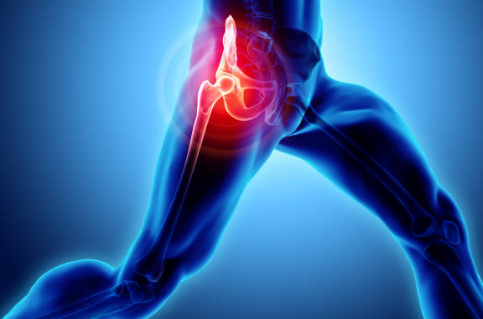

고관절 통증은 다양한 원인으로 인해 발생할 수 있으며, 일상생활에 큰 불편을 초래할 수 있습니다. 이 통증은 나이와 상관없이 누구에게나 발생할 수 있지만, 특히 고령층에서 자주 나타나며, 증상은 앉거나 서 있을 때의 통증, 걸음걸이의 변화, 운동 범위의 제한 등으로 다양합니다. 이러한 통증은 고관절의 구조적인 문제나 외상, 염증 등 여러 원인에 의해 유발될 수 있으며, 심한 경우 수술이 필요할 수도 있습니다.

고관절 통증 증상

고관절 통증은 다양한 원인으로 발생할 수 있으며, 여러 증상이 나타날 수 있습니다.